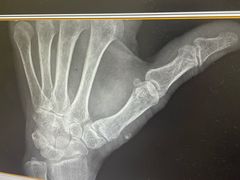

• -上海市普陀区中心医院

路人飞 | 24-09-10

报错